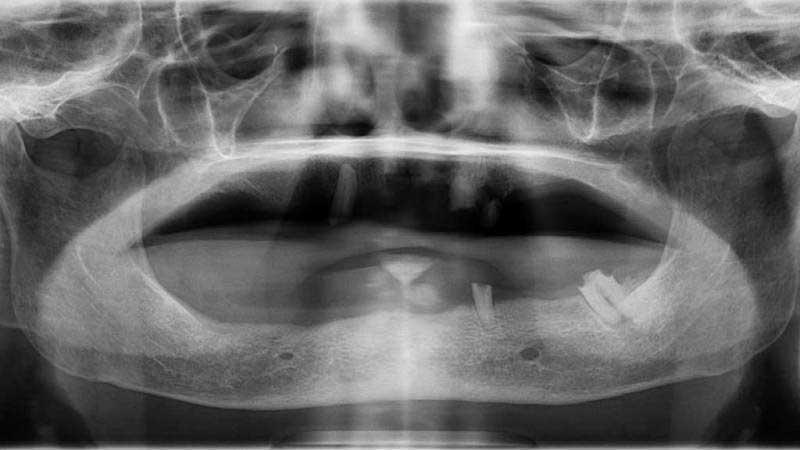

案例1